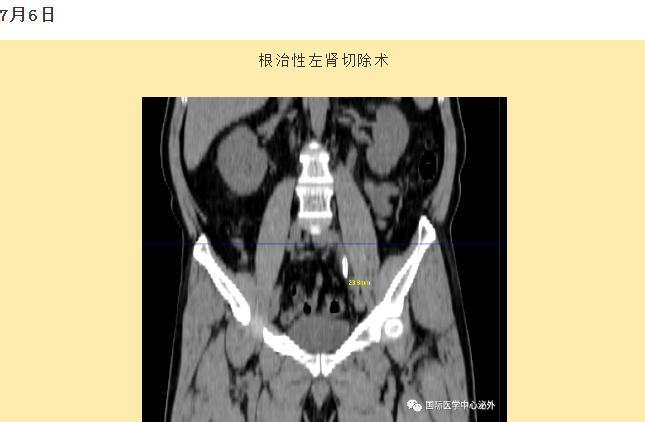

西安國(guó)際醫(yī)學(xué)中心醫(yī)院順利完成了達(dá)芬奇Xi(第四代)機(jī)器人裝機(jī)。7月6日—7月15日,泌尿外科成功完成了達(dá)芬奇Xi(第四代)機(jī)器人手術(shù)6例,標(biāo)志著科室微創(chuàng)外科邁入新時(shí)代,造福萬千患者。